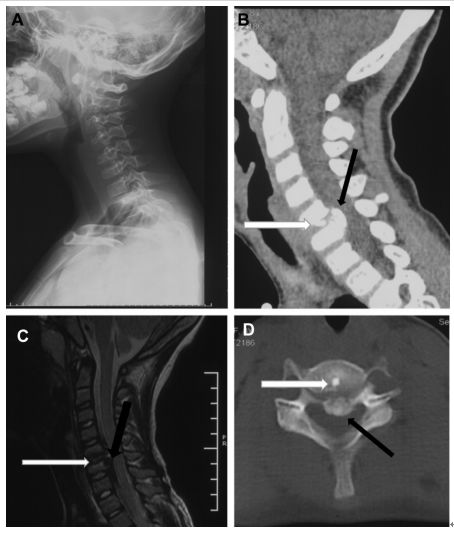

32岁男性,颈肩部疼痛1月,喝水时轻度吞咽困难伴颈椎活动受限,无发热,化验指标正常,经非甾体抗炎药和秋水仙碱治疗后症状改善,4月后复查颈椎侧位片(D,E)钙化消失。(PMID: 25941110)